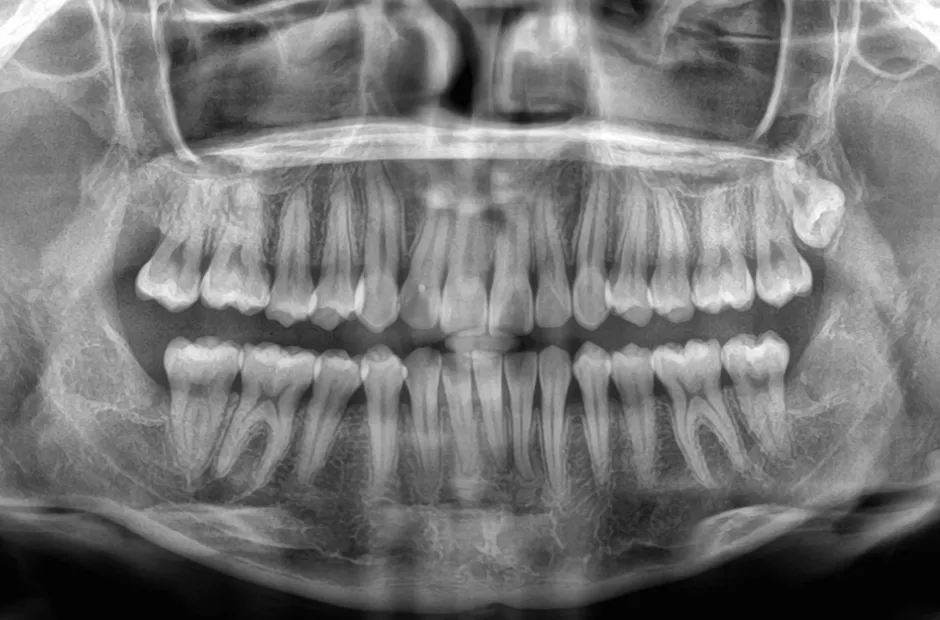

| 診断名・主訴 | 下顎前突、叢生 |

|---|---|

| 年齢・性別 | 23歳・女性 |

| 治療期間・回数 | 3年 |

| 治療に用いた主な装置 | 上顎5,5 下顎4,4 |

| 抜歯部位 | 舌側矯正 |

| 治療費 | 100万円(税抜) |

| リスク・副作用 | 装置による違和感・疼痛・歯肉退縮・歯根吸収・虫歯のリスクなど |

治療前